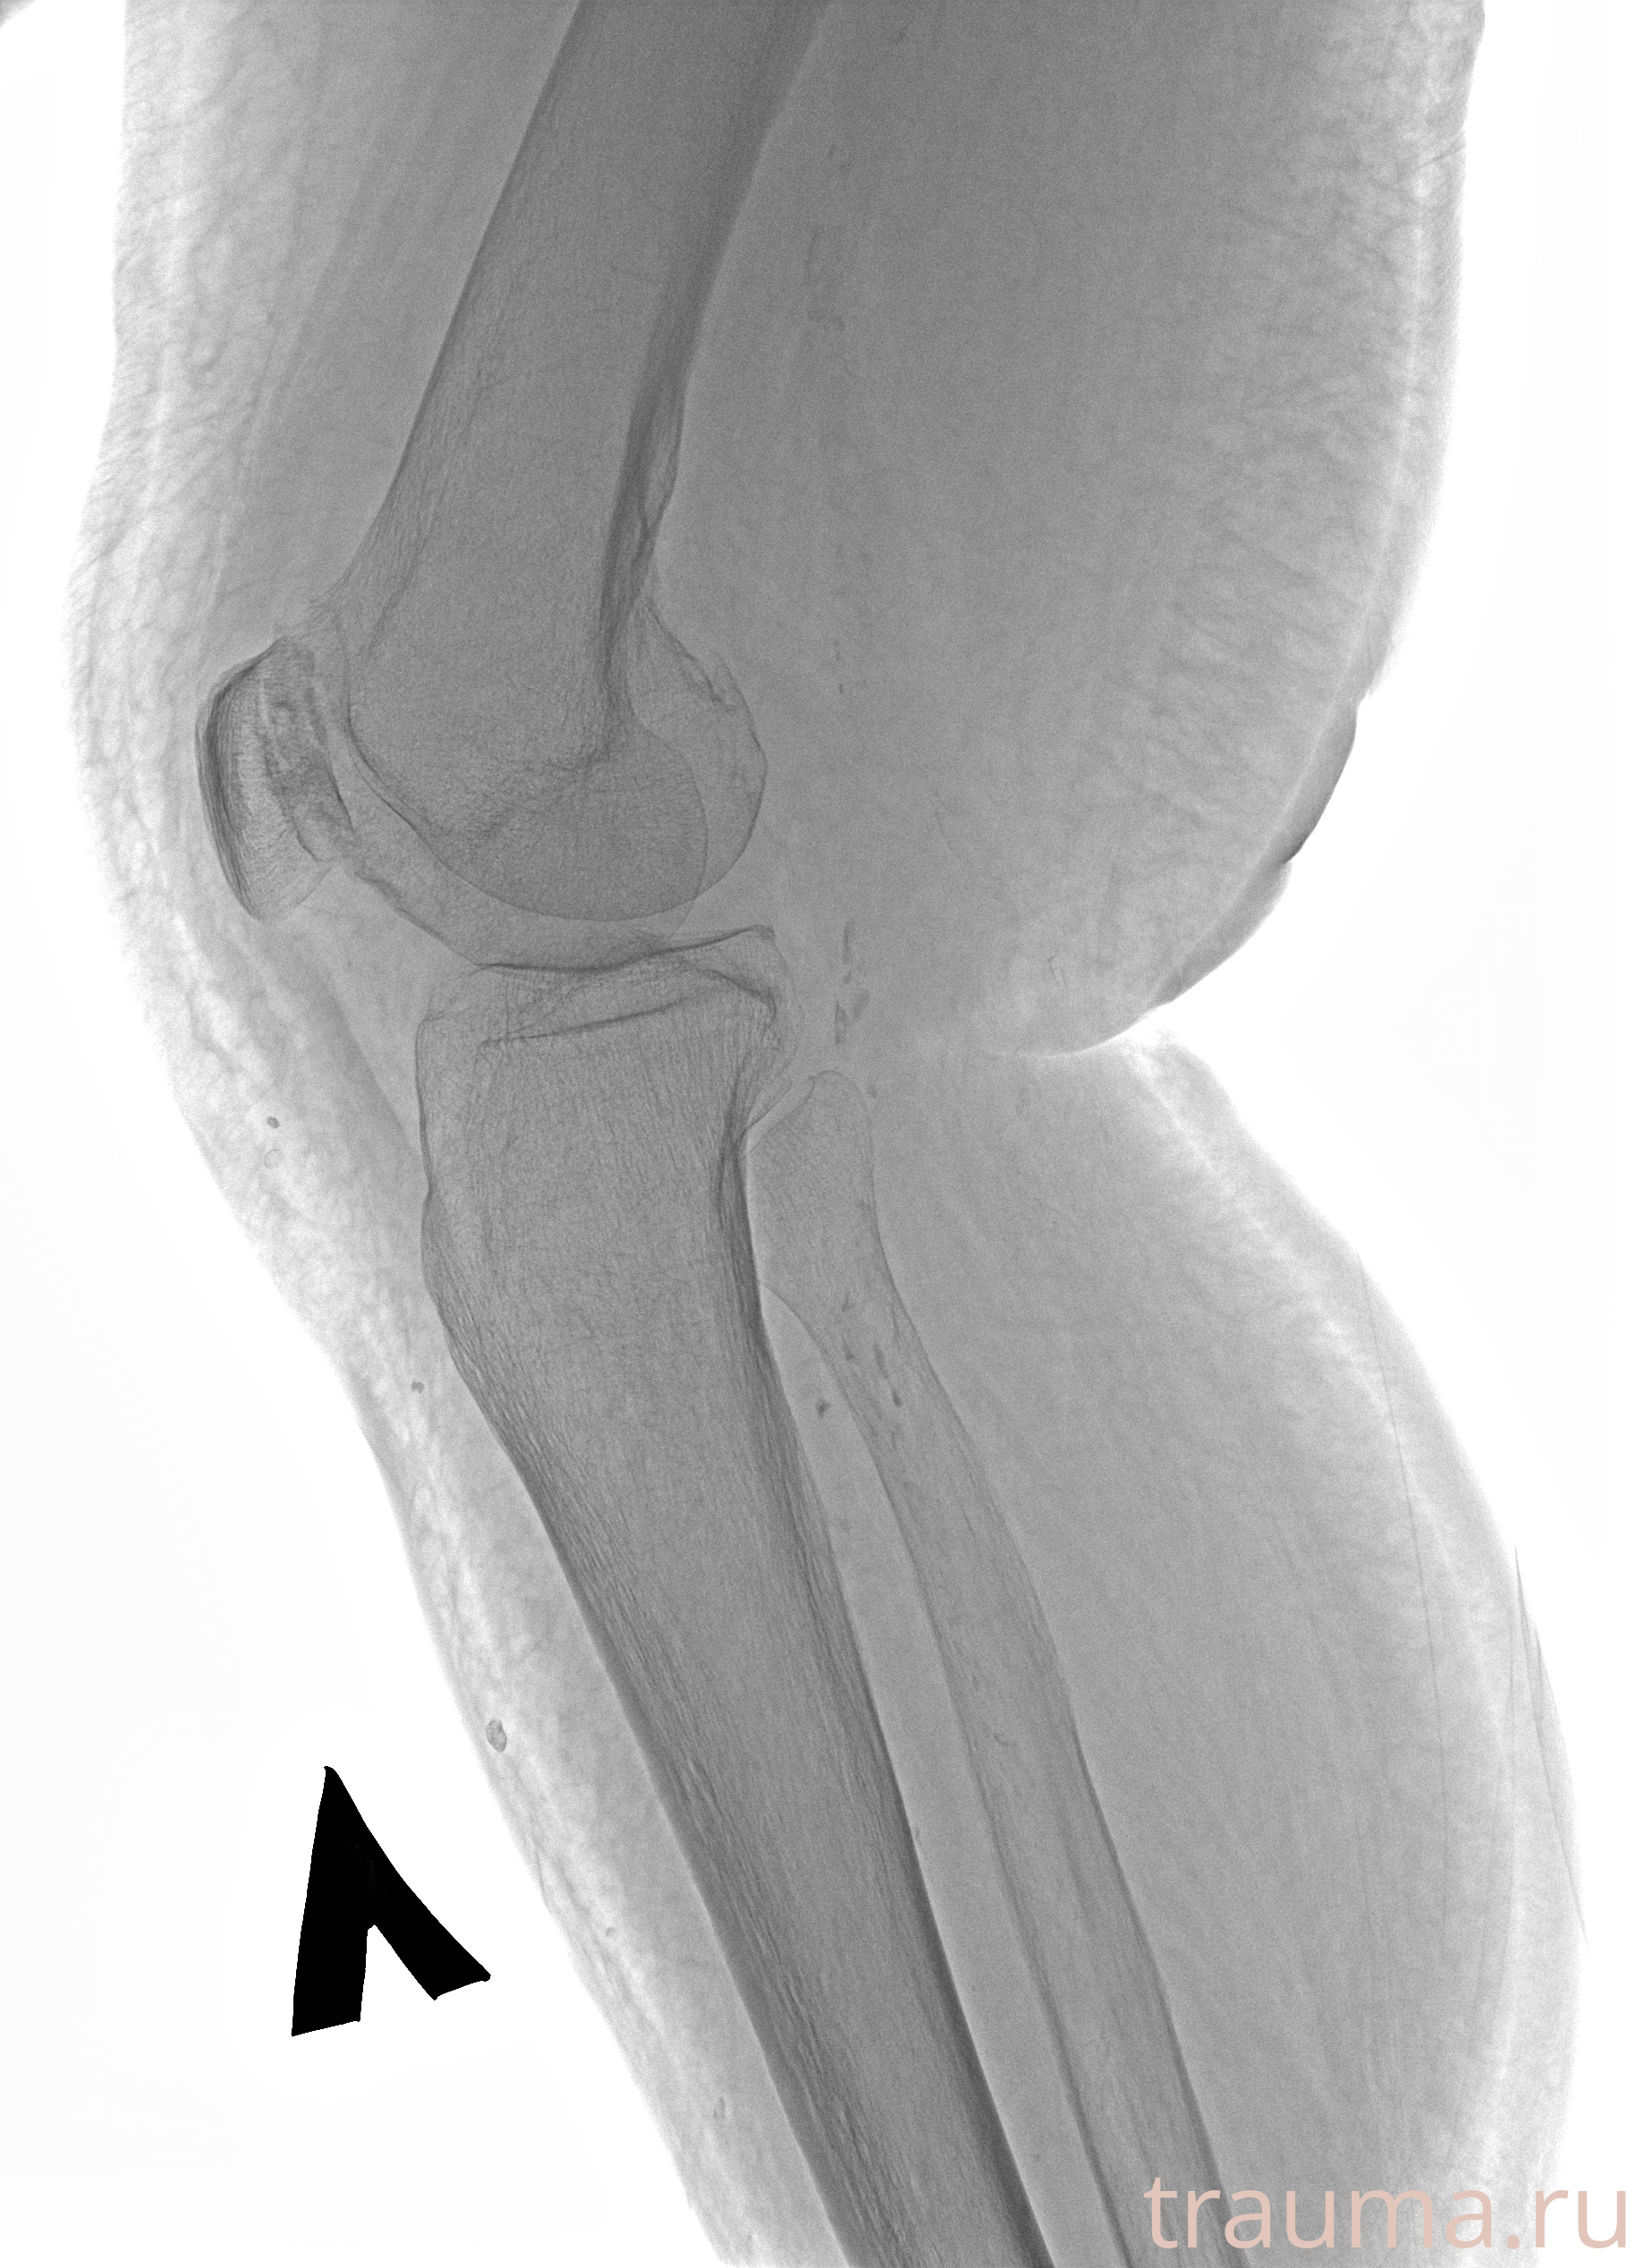

Рентген на дому: по вашему адресу приезжает врач-рентгенолог, травматолог-ортопед с мобильным рентгеновским аппаратом, проводит диагностику травмы или заболевания, делает необходимые рентгенограммы, дает рекомендации по дальнейшему лечению. Получить качественные снимки в домашних условиях возможно благодаря уникальной методике, разработанной МосРентген Центром для института  Склифосовского